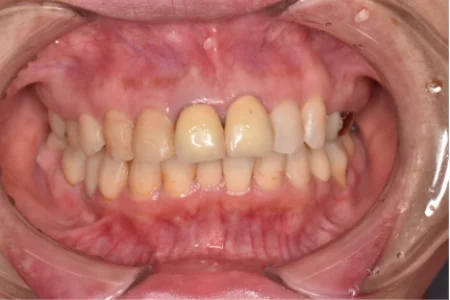

治療前

| ご相談内容 | 「上の前歯3本が黄ばんでおり、前歯全体も点々と色がついていて気になる。歯を白くしたい」とご相談をいただきました。 |

| カウンセリング・診断結果 | 右上の中切歯(1番)と左上の中切歯(1番)は保険で作製した被せ物が入っており、その内の1本は表面のレジンが剥がれて、中の金属が透けて見えていました。 また、被せ物の内側で虫歯が進行している可能性があり、患者様にもその旨をお伝えしました。 右上側切歯(2番)は、過去に神経の治療をしたことが原因で変色していました。 |